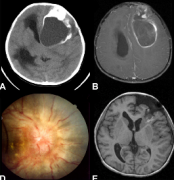

室管膜瘤是一类胶质肿瘤,通常发生于脑室系统的室管膜衬里内或附近,认为其起源于脑室下区的放射状胶质细胞。室管膜瘤较常发生于颅后窝与四脑室相连,或发生于脊髓髓内,有...

室管膜瘤临床症状有哪些?室管膜瘤是⼀类胶质肿瘤,通常发⽣于脑室系统的室管膜衬⾥内或附近,认为其起源于脑室下区的放射状胶质细胞。室管膜瘤较常发⽣于颅后窝与四脑室相...